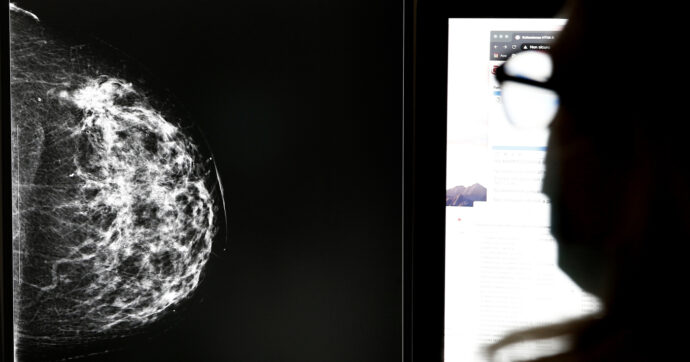

Almeno 2000 donne sarebbero coinvolte nell'"errore tecnico" che ha portato delle pazienti a scoprire solo dopo anni di avere un tumore al seno in fase avanzata

Centinaia, forse migliaia di donne andaluse non sono mai state avvisate dei risultati sospetti delle loro mammografie. Tanto da aver scoperto solo dopo anni di avere un tumore al seno in fase avanzata. Quello che sembrava un errore tecnico si è rivelato un colossale fallimento istituzionale, che oggi travolge la Junta de Andalucía, governata dal Partido Popular (PP), il partito di centrodestra che guida la regione dal 2019 con il presidente Juan Manuel Moreno Bonilla.

Il programma di “cribado” (screening) del cancro al seno è uno dei principali strumenti di prevenzione del sistema sanitario spagnolo. Ogni due anni, le donne tra i 50 e i 69 anni vengono invitate a sottoporsi a una mammografia gratuita. Se l’esame mostra segni sospetti, la paziente deve essere contattata entro poche settimane per ulteriori indagini.